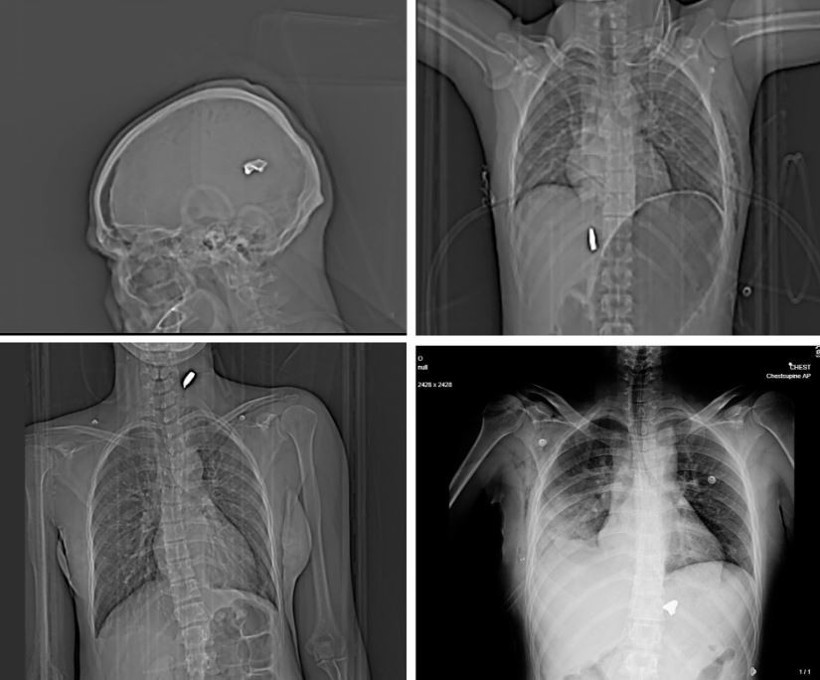

İngiliz gazetesi The Guardian ve söz konusu bilgilerin doğruluğunu teyit eden Factnameh'nin gerçekleştirdiği ortak araştırmada, ülkenin büyük şehirlerinden birinde yer alan bir hastaneden elde edilen 75'ten fazla röntgen ve bilgisayarlı tomografi görüntüsü yayınlandı.

Bu görüntüler, güvenlik güçlerinin yüksek kalibreli silahlar ve birdshot mühimmatı kullandığına dair iddiaları destekliyor. Röntgenlerin büyük bölümünde, protestoculara karşı “birdshot” olarak adlandırılan mermilerin kullanıldığı belirtiliyor.

Balistik uzmanları, bazı röntgen görüntülerinde vücutta bulunan mermilerin AK-47 ve KL-133 gibi taarruz tüfeklerine ait mermilere benzer olduğunu aktardı.

Bir başka uzman, görülen yaralanmaları “savaş alanında sıkça karşılaşılan türde” olarak tanımladı.

Saldırıların çoğunlukla yüz, göğüs ve genital bölgelerde yoğunlaştığı da dikkatlerden kaçmadı. 2022 yılında başlayan “Kadın, Yaşam, Özgürlük” protestolarında da benzer yaralanma örüntüleri gözlenmişti.

Guardian'a konuşan İranlı doktorlar, protestocuların özellikle göz, göğüs ve genital bölgelerinin hedef alındığını ifade etti. Bazı sağlık çalışanları, pek çok hastada görme kaybı meydana geldiğini ve bunu yaşayanlar arasında çocukların da bulunduğunu belirtti.